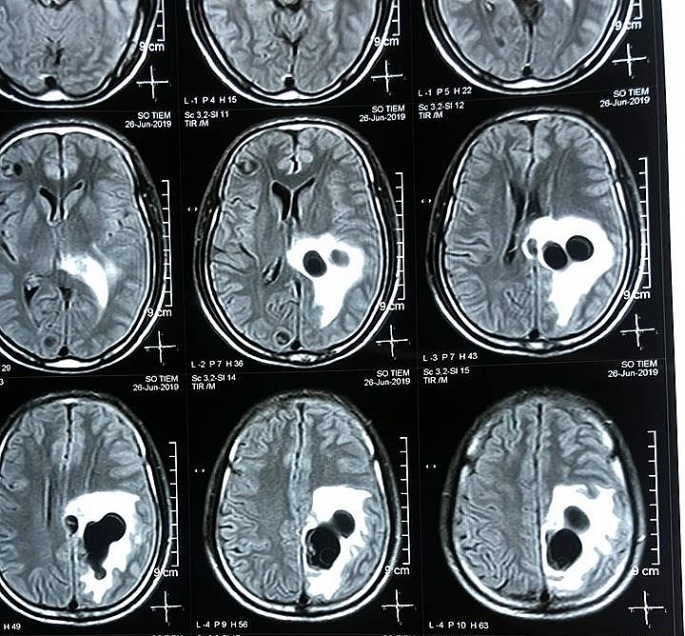

| Hình ảnh chụp CT cho thấy có 5 ổ nang sán làm tổ trong não nam bệnh nhân này. |

Kết quả chụp CT tại Bệnh viện Hữu nghị Đa khoa Nghệ An cho thấy có 5 ổ sán nằm rải rác trong não nam bệnh nhân này. Trong đó có một ổ sán lớn trên đỉnh gây phù não.